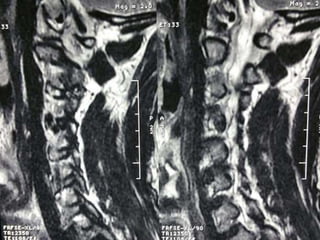

77 year old woman with h/o hand weakness/numbness/ataxia

Prior acdf 14 years ago

77 year oldwoman with h/o hand weakness/numbness/ataxia Prior acdf 14 years ago